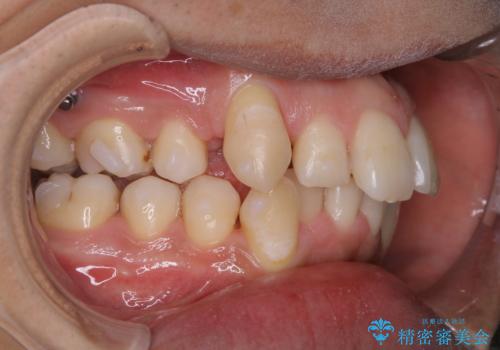

- インビザラインでの矯正治療中に、アタッチメント周囲のステインが気になるとのことでした。PMTC30分コースで、特に見える表側のステイン除去を行いました。

マウスピース矯正インビザライン治療では、歯の表面にアタッチメントという突起を設定します。(アタッチメントは歯の動きを効率的に移動するためのものです)

アタッチメントが歯に付くと、表面が凸凹し磨き残しが多くなったりと、プラークや歯石・着色がつきやすくなることがあります。